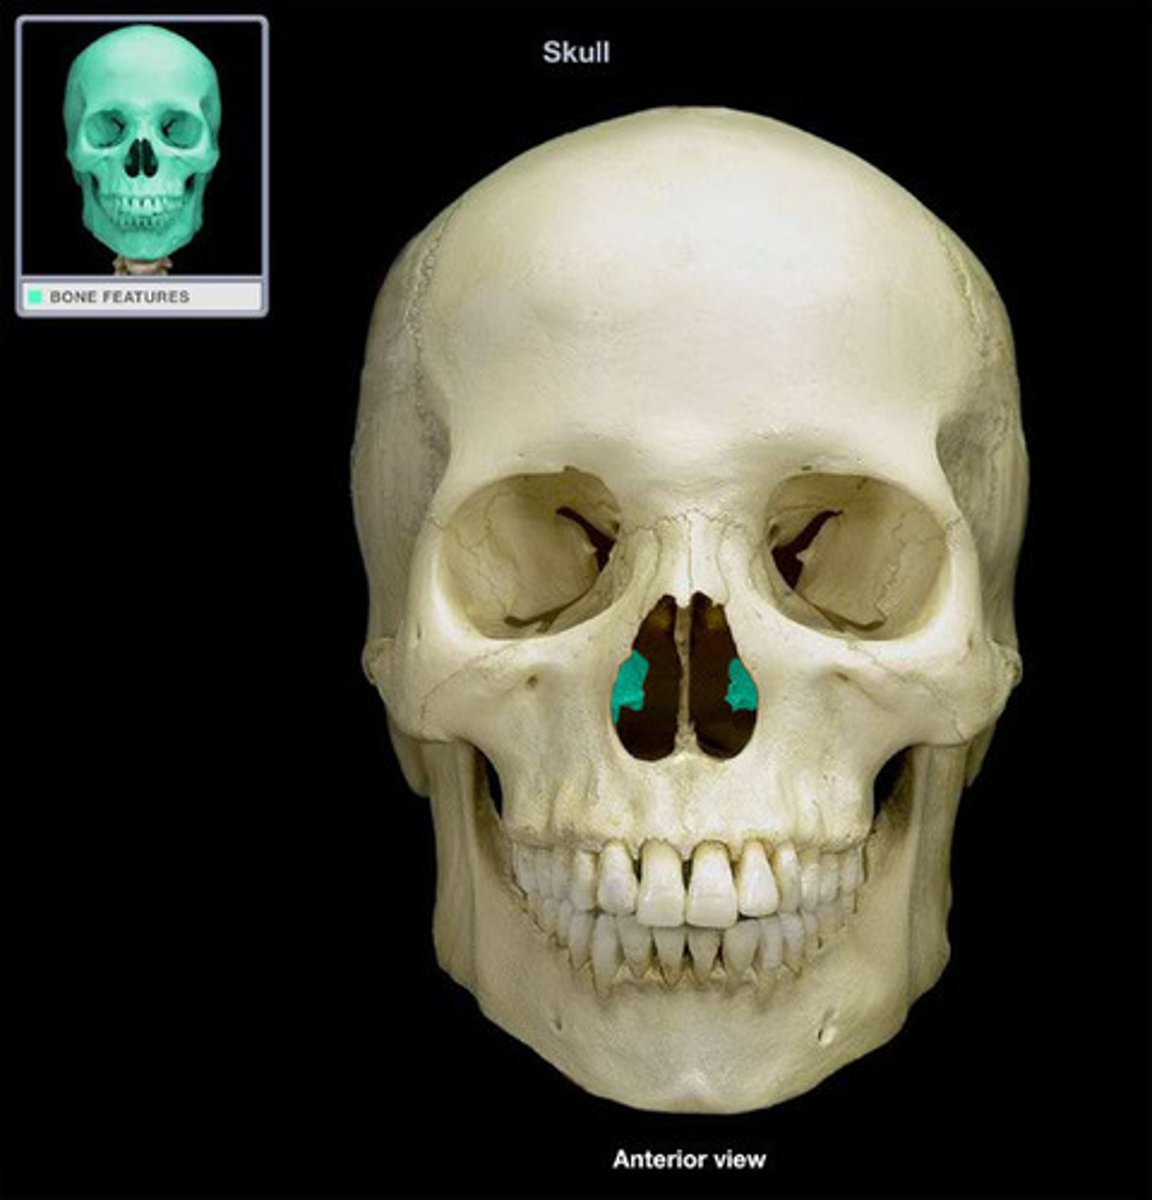

Superior and Middle Nasal Conch

Vomer

Inferior Nasal Concha